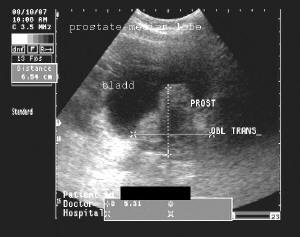

Well, after months of milking that particular teat it seems to have run dry, so the good Dr Wright has moved on to another, namely benign prostatic hyperplasia (BPH). The standard treatment for this common (well, amongst grumpy old men, anyway) ailment is a drug called finasteride, variously marketed under other names, such as Proscar and Propecia (in its other use as a cure for male-pattern baldness).